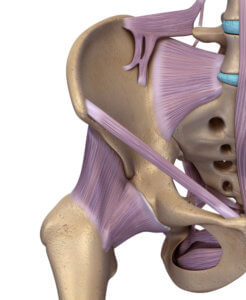

髖關節位於盤骨下端接著大腿骨的位置。這是一個轉動關節,能令我們可以向前、向外、向內、向後提腿。 大腿骨的頂部及盤骨內有一個軟骨組織來幫助減少承托身體的壓力和大腿活動的磿擦。髖關節外層有不同 韌帶及肌肉互相鞏固及承托髖關節活動及重量。( 圖ー至圖三)